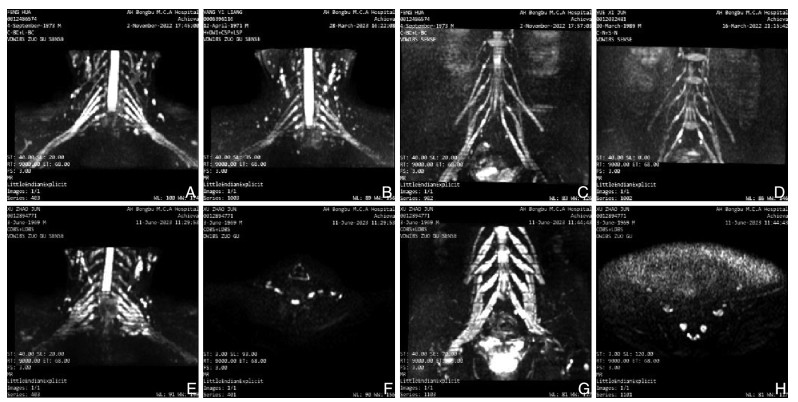

Significance and mechanism of neuroultrasound combined with neuromagnetic resonance imaging in the diagnosis and treatment of Guillain-Barré syndrome

SHI Peng, WU Xinyu, HUAI Yushui, SONG Hongwei, NIAN Di

2025, 23(8): 1292-1297. doi: 10.16766/j.cnki.issn.1674-4152.004118

Abstract:

Objective  To explore the significance and mechanism of neuroultrasound and neuromagnetic resonance imaging in the diagnosis of Guillain-Barré syndrome (GBS).  Methods  A total of 43 GBS patients who were first diagnosed at the First Affiliated Hospital of Bengbu Medical University from October 2021 to February 2025 were enrolled, and 24 patients with normal physical examination were enrolled as control group. Based on neurophysiological examinations, the GBS were classified into two subtypes: acute inflammatory demyelinating polyneuropathy (AIDP) and acute motor axonal neuropathy (AMAN). Neuroultrasound and neuromagnetic resonance imaging were performed on all subjects. The cross-sectional area of the cervical nerve roots and peripheral nerves (CSA) was measured by neuroultrasound, and the CSA of the cervical nerve root and lumbar sacral nerve root was measured by neuromagnetic resonance imaging. The degree of neurological impairment in GBS was assessed using the GBS disability scale scores (GDSS), and the correlation between CSA values and the degree of neurological deficit was evaluated. Peripheral venous blood was collected, and the levels of pyroptosis-related inflammatory factors in peripheral blood were measured using ELISA.  Results  Compared with the control group, the nerve roots and peripheral nerves of the limbs in the AIDP group and the AMAN group were thickened, and the CSA value was increased. Among them, nerve ultrasound showed that there were statistically significant differences in C5 and C6 among the three groups (H=20.216, P < 0.001; H=12.452, P=0.002), and the magnetic resonance imaging results showed that compared with the AMAN group and the healthy control group, the CSA values of C4-C8 and L3-S1 in the AIDP group were significantly increased, and the differences were statistically significant (P < 0.01). The CSA value of peripheral nerves was positively correlated with the degree of neurological deficit (P < 0.05). Pyroptotic inflammatory factors were higher than those in the control group, and the difference was statistically significant (P < 0.05).  Conclusion  The elevated CSA values of nerve roots and peripheral nerves, as well as neurological deficits in GBS, may be associated with the inflammatory cascade triggered by pyroptosis pathway activation. The detection of peripheral blood inflammatory cytokines combined with neuroimaging may facilitate early diagnosis of GBS and provide novel insights for its clinical management.